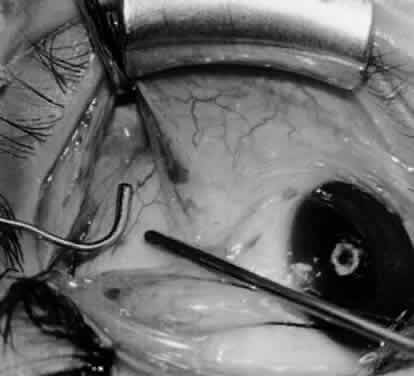

Fig. 10. The inferior oblique muscle is placed on the Green muscle hook. The exposed insertion is ready for myotomy, myectomy, disinsertion, placement of sutures for recession, or removal for the extirpation procedure.

Fig. 11. Sutures are placed into the insertion of the inferior oblique muscle before it is sectioned from the globe for the recession procedure.

Fig. 12. An Aebli scissor is placed beneath the inferior oblique muscle insertion before it is sectioned from the globe.